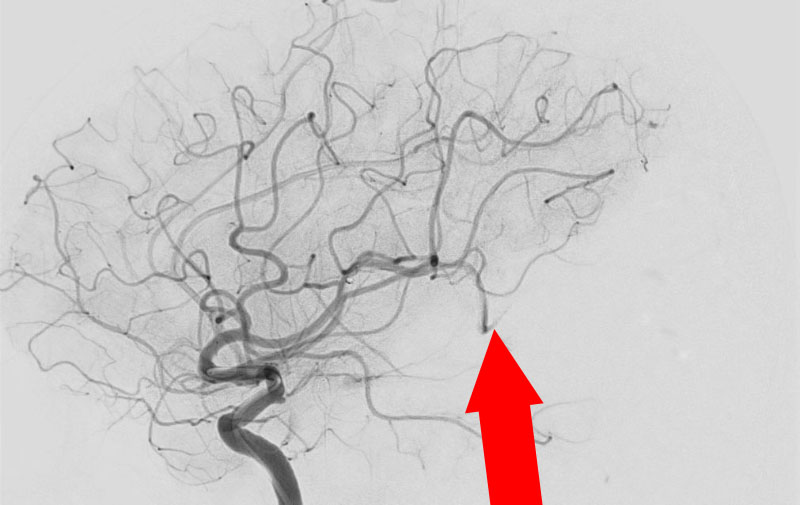

No.1620 手術前